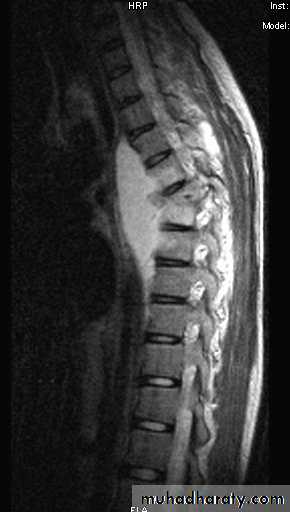

In T B spine

BACKACHE

Kyphosis (gibbus).

Occasionally the presenting feature is weakness or loss of sensibility in the lower limb.

In neglected cases patient presented with paralysis (pott’s paraplegia).

T B spondylitis may appear as localized bone erosion and collapse across an intervertebral disc space

There may be soft tissue traces of paravertebral abscess.